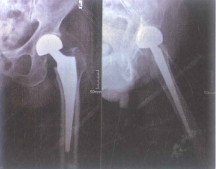

Hình 4.20. Hình ảnh X-quang sau mổ thay khớp háng (T) bán phần

Hình 4.21. Hình ảnh X-quang sau mổ thay khớp háng (T) toàn phần

1.2.4. Điều trị phẫu thuật thay khớp háng bán phần

Là phương pháp thay chỏm, cổ xương đùi bằng dụng cụ nhân tạo và giữ lại ổ cối tự nhiên.

1.2.5. Điều trị thay khớp háng toàn phần

Thay khớp háng toàn phẩn là phương pháp thay cả chỏm, cổ xương đùi và ổ cối bằng vật liệu nhân tạo.